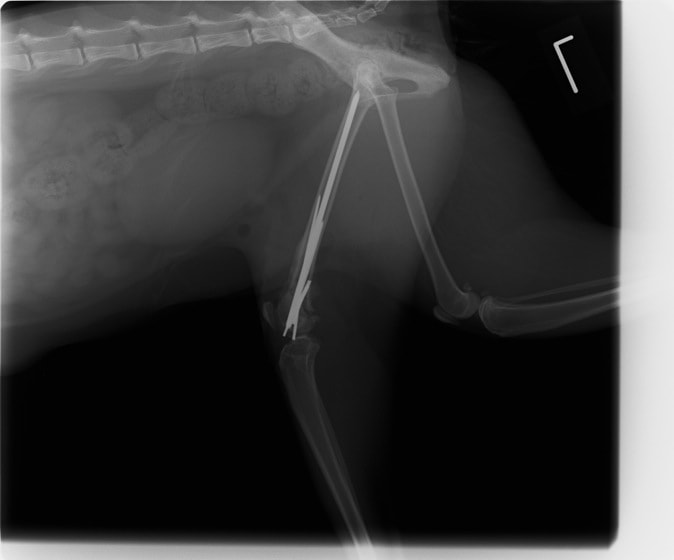

脊髄の減圧、脊柱管の再構築・安定化を目的に、片側椎弓切除術およびMatrixMANDIBLE Plateによる椎体固定を実施しました。

隣接椎体を架橋するようにプレートを設置しました。

術後レントゲン写真